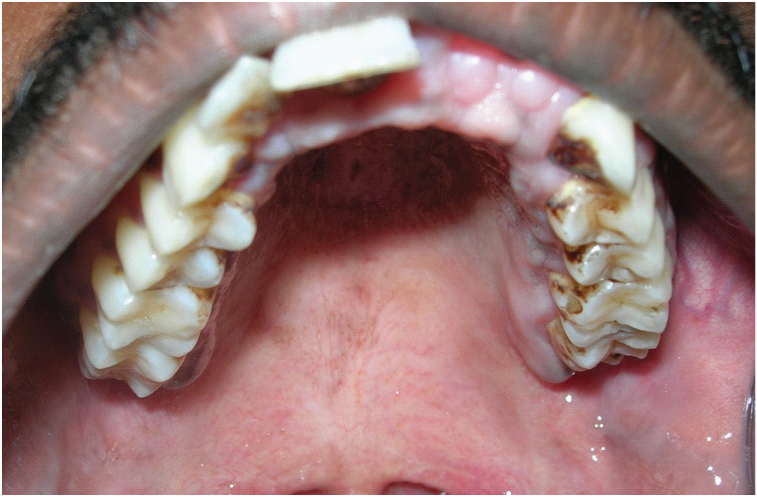

[Table/Fig-3] showing the normal morphology of crowns of the maxillary teeth. [Table/Fig-4] showing the normal morphology of crowns of the mandibular teeth. Full mouth intraoral periapical radiograph revealed complete root resorption in relation to 11, 12, 41 and 42; cervical resorption in 15, 33, 34 and 43, 44; apical resorption in 16, 24, 25 and 26. Resorption in both apical and cervical region was noticed in relation to 35, 36 and 46. Panoramic radiographs showed multiple ill defined radiolucent areas in apical third and cervical region of all teeth in varying degree. Lateral view of skull showed no evidence of any skull changes. In [Table/Fig-5] intraoral periapical radiograph showing complete root resorption in relation to 11 and 12. In [Table/Fig-6] intraoral periapical radiograph showing complete root resorption in relation to 41 and 42. In [Table/Fig-7] intraoral periapical radiograph showing cervical resorbtion in relation to 15 and apical root resorption of mesial and distal roots in relation to 16. Loss of PDL space in 17 can be appreciated.

Showing the normal morphology of crowns of the maxillary teeth